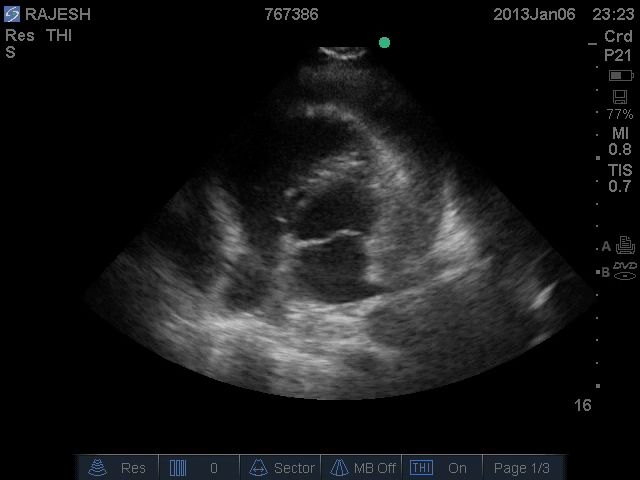

ECHO

[on admission]: No RWMA. Valves normal

Normal biventricular function. LVEF = 55-60 %

No clots. Pericardial effusion + (2 cm in any direction)

No intra-cardiac clots. IVC dilated. Respiratory movements present

[pre-discharge]: Mild-to-moderate pericardial effusion with strands

No RA / RV collapse. No RWMA. Normal LV & RV function. LVEF - 55-60 %

Normal valves. Trivial mitral regurgitation